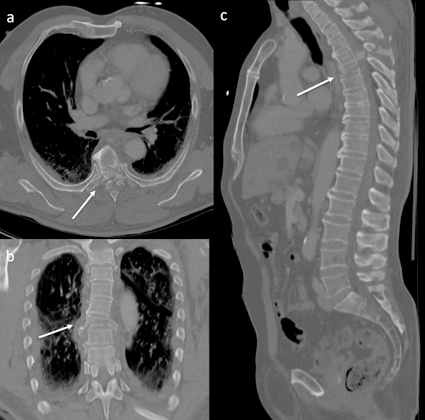

Bei Gelenkerkrankungen ist die CT mit Ausnahme von röntgenologisch nicht ausreichend beurteilbaren Frakturen und dem V. a. freie Gelenkkörper relativ selten indiziert. Im Gegensatz dazu sind traumatische und tumorbedingte (z. B. Knochenmetastasen) Wirbelsäulenerkrankungen etablierte CT-Indikationen. So gehört für Traumazentren das Polytrauma-CT vom Schädel bis zum mittleren Oberschenkel unmittelbar nach Einlieferung eines schwerverletzten Patienten zu den geforderten Zertifizierungsvoraussetzungen.

Der CT ist eine wichtige Methode zur präoperativen Planung und postoperativen Materialkontrolle. Bei Wirbelkörpermetastasen ermöglicht die CT die Abschätzung des Frakturrisikos und der Ausdehnung von Weichteiltumoranteilen in den Spinalkanal (Spinalkanaleinengung mit drohender Querschnittslähmung), wobei dieses Befunddetail sich noch besser mit der MRT diagnostizieren lässt. Auch kleine Knochenmetastasen sind u. U. nur MR-tomografisch oder mit der Skelettszintigraphie nachweisbar.